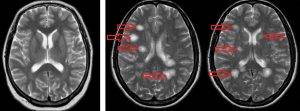

Признаки нарушений проводимости по нервам (слабость / парез в конечностях, потеря рефлексов, нарушения чувствительности, периферическая невропатия), сильные головные боли, ригидность затылочных мышц, менингит, нарушения в работе черепно-мозговых нервов (например, изменяются восприятие запаха/вкуса; трудности при жевании, глотании, или разговоре; дисфония или проблемы в голосовых связках; паралич лицевого нерва – паралич Белла; головокружение/обморок; опущение плеч; неспособность повернуть голову; световая или звуковая чувствительность. Кроме того, возможны также изменение слуха; девиация глазного яблока, птоз века, инсульт, нарушения сна, интеллектуально-мнестические нарушения (нарушения фиксационной памяти, концентрации внимания, выполнении простых арифметических действий) нарушения поведения (депрессия, изменение индивидуальности).